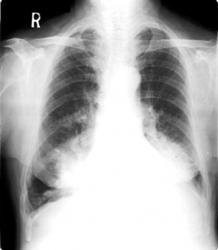

La radiografia qui sopra si riferisce a un soggetto che ha

contratto la polmonite lipoidea. L'immagine è simile a quelle

che mostrano situazioni legate a neoplasie. |